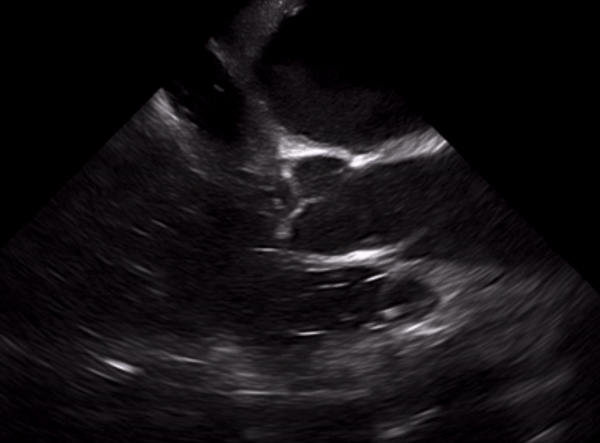

The midesophageal 4-chamber view (Fig. 2) is the most intuitive view to obtain, and is similar in nature to the common TTE apical four chamber view. This view is obtained by advancing the TEE probe to the thoracic esophagus and orienting the multiplane at 0-20° in neutral flexion, after which all four chambers can be visualized. This view provides excellent visualization of both ventricles and atria as well as the tricuspid and mitral valves in the same plane. It is important to avoid foreshortening the ventricles, and mild retroflexion of the probe is sometimes necessary. This view is useful for evaluation of right and left ventricular systolic function as well as size, and is the preferred view to evaluate for the presence or absence of a perfusing rhythm during a pulse check.

Figure 2: Mid-esophageal 4-chamber view

Adapted from Arntfield R, Pace J, McLeod S, et al. Focused transesophageal echocardiography for emergency physicians-description and results from simulation training of a structured four-view examination. Crit Ultrasound J. 2015;7(1):27.